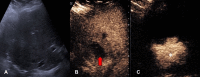

The introduction of ultrasound contrast agents has rendered contrast-enhanced ultrasound (CEUS) a valuable complementary technique to address clinically significant problems. This pictorial review describes the use of CEUS guidance in abdominal intervention and illustrates such application for a range of clinical indications. Clinical application of CEUS discussed include commonly performed abdominal interventional procedures, such as biopsy, drainage, nephrostomy, biliary intervention, abdominal tumor ablation and its subsequent monitoring, and imaging of vascular complications following abdominal intervention. The purpose of this article is to further familiarize readers with the application of CEUS, particularly its specific strength over alternative imaging modalities, in abdominal intervention.